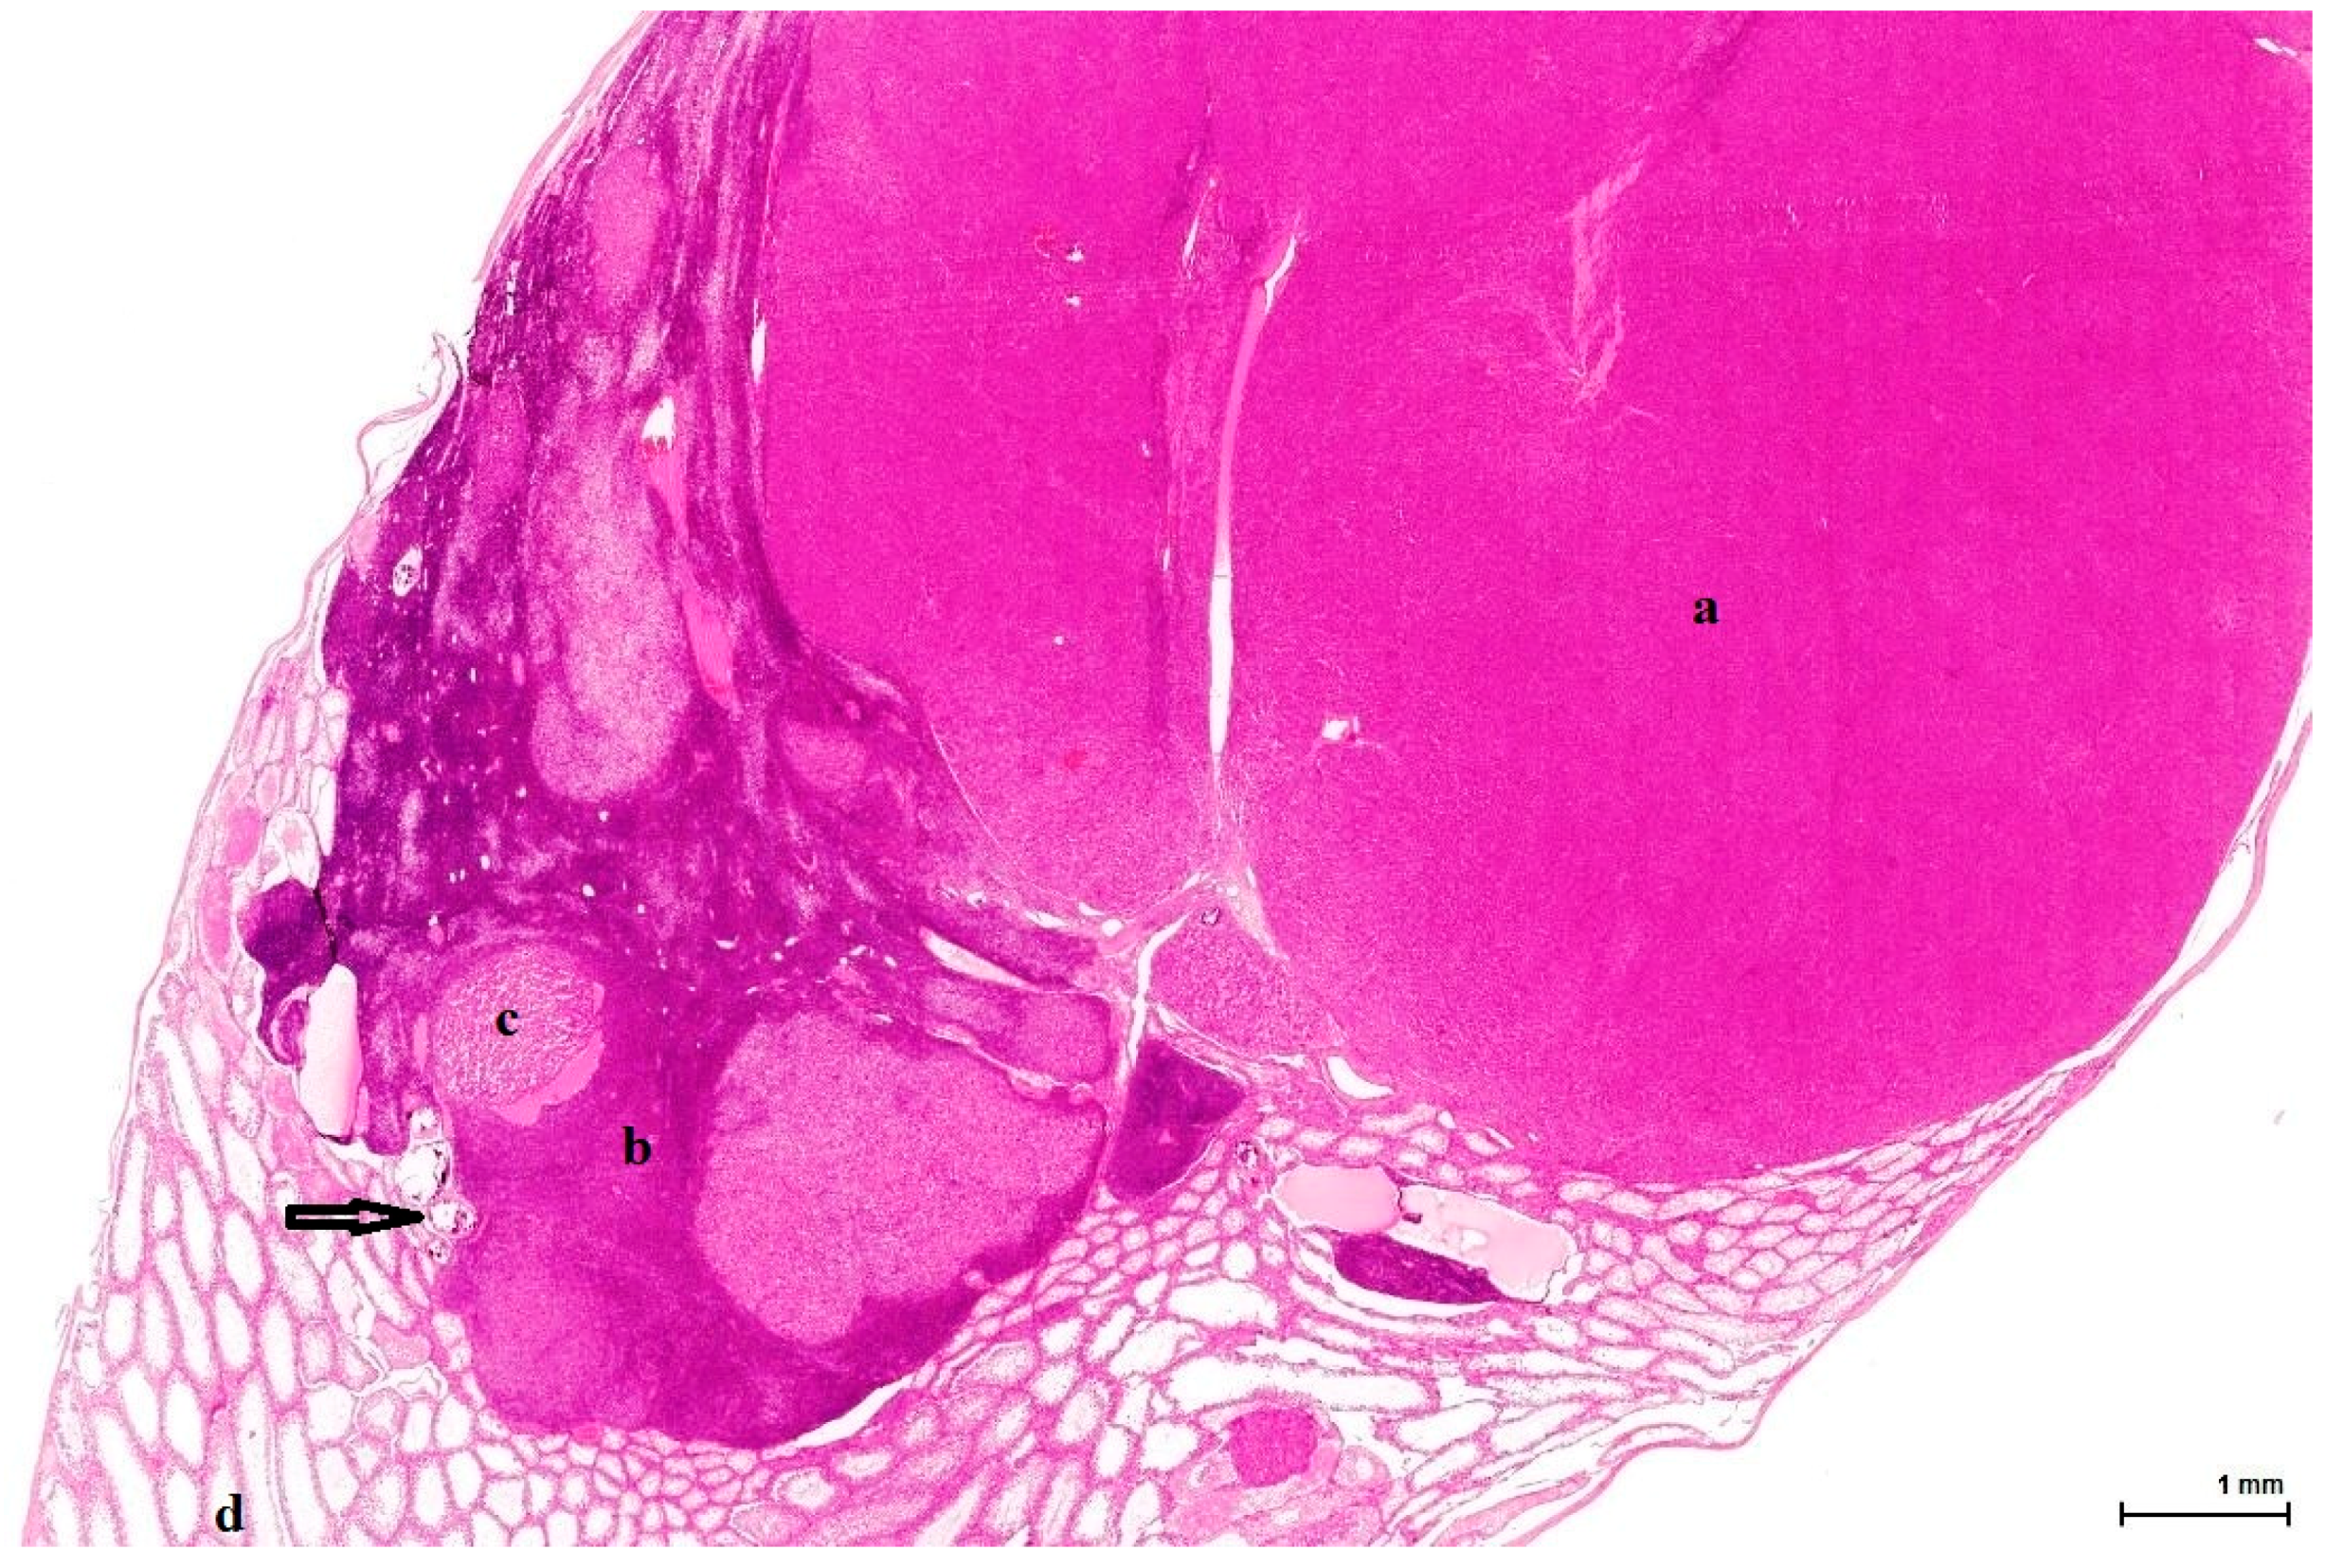

Figure 1. OTA-treated Case 2 with large solid nodule composed of eosinophilic cells (a); adjacent sheets of (b) basophilic (dark blue) cells including small (c) lobules of foamy cells (light eosinophilic). Background: mostly atrophic testicular parenchyma (d) with focal calcification (arrow). (H&E).

All cases show enlarged testicles, containing tumours measuring up to 23 mm in the longitudinal sections, well demarcated but not encapsulated, almost completely replacing the whole testis. The tumour invasion front is of pushing type, compressing the minimally remaining testicular parenchyma, which consists of a few normal or atrophic seminiferous tubules, with frequent dystrophic calcification. All tumours are organ-confined; there is no evidence of infiltrative growth or tunica involvement (Figure 1).

These are nodular cellular proliferations, usually multinodular, frequently coalescent nodules, usually solid with cystic spaces (empty or filled with proteinaceous material), composed of sheets of large, polyhedral cells with abundant eosinophilic cytoplasm, which is frequently lipidized. The nuclei are uniform, round, with evenly distributed chromatin and occasional small nucleoli; some are mitotically active. Admixed with these large cells are smaller ones, with little, unremarkable cytoplasm and small hyperchromatic nuclei. These two cell populations can form separate individual nodules, or they can intermingle, with no sharp demarcation, as there seems to be an imperceptible transition from one to the other. The large, clear cells with foamy, micro- and macrovesicular cytoplasm contain lipid vacuoles and sometimes golden brown lipofuscin pigment identified as purple red on a PAS stain (Figure 2). The small cell type has a basophilic appearance, mimicking a lymphoid infiltrate (Figure 3). The stroma is scant and occasionally hyalinised, with a rich vascular network; extensive haemorrhaging is present in some cases.